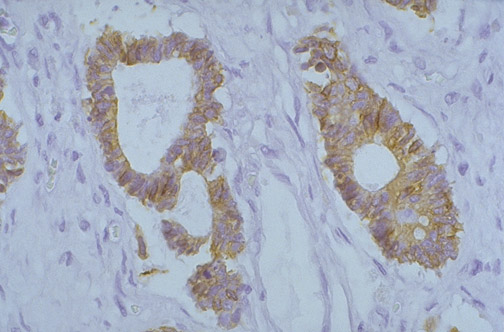

Image 2.4

This is the microscopic appearance of the mass lesion with immunohistochemical staining for CK-20, a form of cytokeration. Note that there is cytoplasmic staining in the lesion.